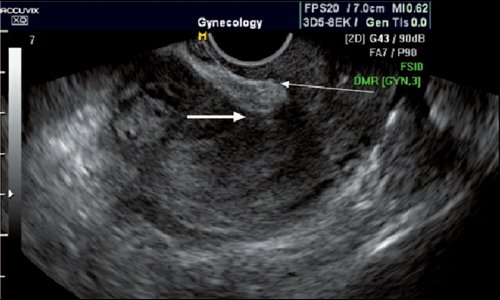

При наличии перечисленных признаков врач чаще всего делает УЗИ диагностику состояния рубца. Поэтому для беременных после кесарева сечения женщин на сроке от 28 -37 недель назначают дополнительное ультразвуковое обследование.

2. В сроках 36-37 недель беременности проводится ультразвуковое исследование рубца с допплерометрией для выявления наличия мышечной ткани в области рубца.

Такое исследование позволяет провести функциональную оценку рубца для возможности проведения естественных родов. Если в области рубца мышечная ткань отсутствует, то роды возможны только оперативным путём!

И никакая толщина рубца, даже если она измерена правильно, не даёт возможности оценки прогноза родов. К сожалению, этот атавизм врачебной практики ещё прочно сидит в головах врачей, особенно в женских консультациях, и они достаточно часто гоняют беременных на УЗИ измерить толщину рубца.